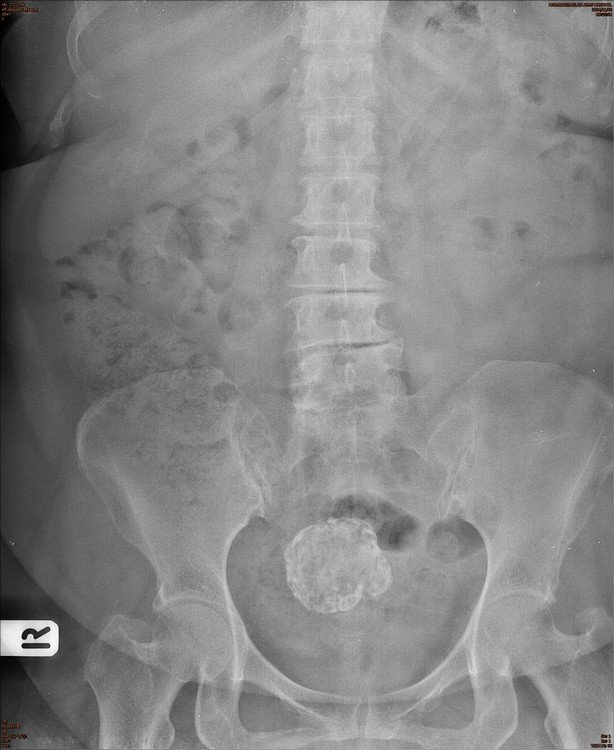

Abdomen : Case 5

History :  A 52-year-old male with abdominal discomfort

Answer : B . Calcified uterine myoma or calcified fibroid

• Conventional radiography :

• Soft tissue mass arising from the pelvis but separate from the urinary bladder

• Amorphous, flocculent calcifications in the pelvis

• May resemble “popcorn” or may calcify the outer rim of fibroid

• Displacement of bowel gas up and out of the pelvis